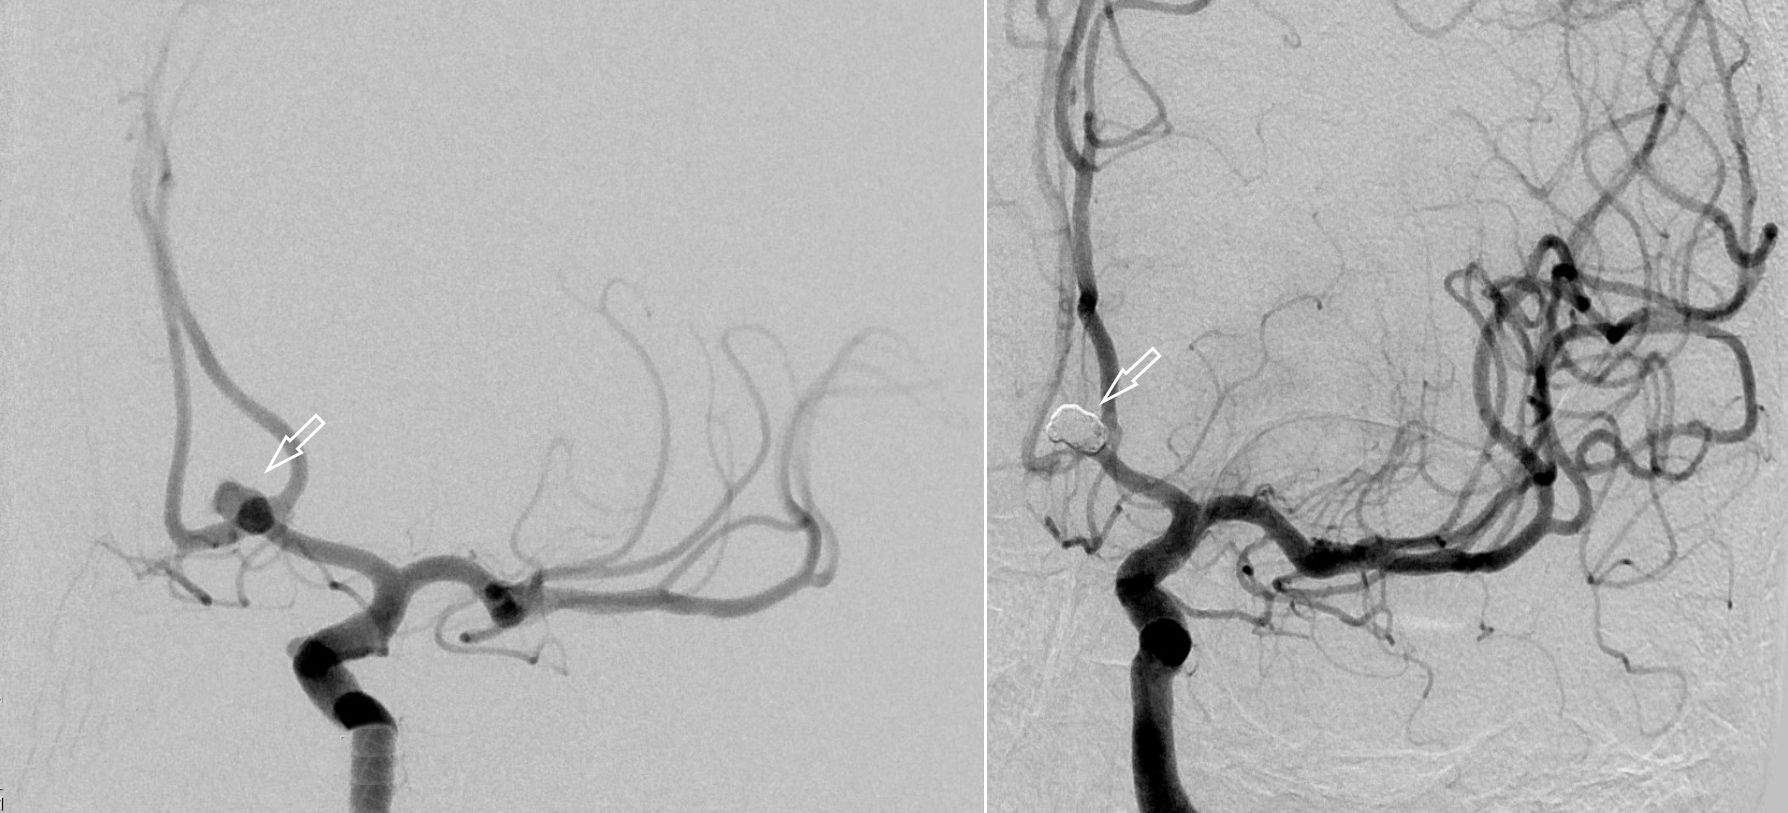

Als schnellste und sicherste Maßnahme gilt das craniale Computertomogramm (CCT). Hier lässt sich eine frische SAB meist zuverlässig darstellen, wobei auch bereits richtungsweisende Befunde, wie das Ausmaß der Blutung und eine eventuelle Lokalisation eines möglichen Aneurysmas bestimmt werden können. Darüber hinaus kann ein Angio-CCT, bei dem zusätzlich Kontrastmittel verabreicht wird und dann die intrazerebralen Blutgefäße gesondert rekonstruiert und dargestellt werden, weitere Informationen liefern. Der sogenannte “Goldstandard” zur Diagnose zerebraler Gefäßmissbildungen ist jedoch die zerebrale Angiographie. Dabei wird mit Hilfe eines speziellen Katheters über die Leisten- oder Armarterie Kontrastmittel gegeben und die zerebralen Blutgefäße hoch selektiv dargestellt. Sollten sich auf dem initialen CCT Zeichen des Hirnwasseraufstaus zeigen, der durch ein Verstopfen der Abflusskanäle durch das neu aufgetretene Blut bedingt ist, ist oft die Anlage einer Hirnwasserableitung nach außen notwendig (externe Ventrikeldrainage).

CT Bildgebung der klassischen subarachnoidalen Blutverteilung nach SAB

3D Darstellung eines Aneurysmas

CT-Angiographie eines gebluteten Aneurysmas

Angiographiesche Darstellung eines Aneurysmas

Angiographiesche Darstellung eines Aneurysmas vor (links) und nach (rechts) dem Coiling